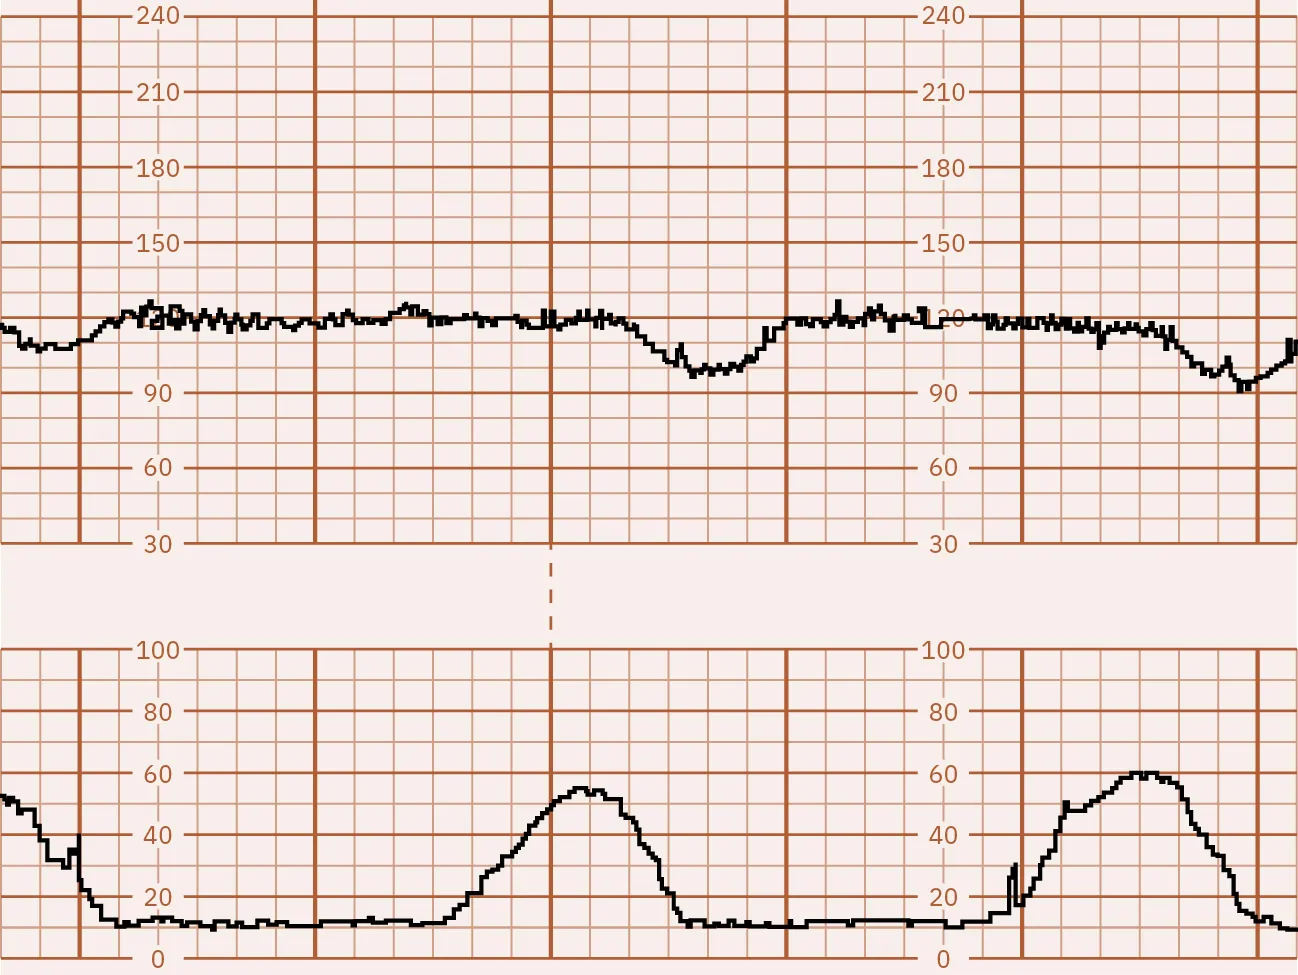

The CST test results are divided into several categories:

• Positive: Late decelerations occur after 50 percent or more of contractions, even if the contraction frequency is less than three in 10 minutes (Figure 13.12).

Fetal monitor tracing graphic depicting positive CST. Top strip displays dips in lines after second strip shows spikes.

Figure 13.12 Positive CST In this illustration, the FHR baseline is 130. The fetal heart rate is at the top and the contractions are on the bottom. This strip shows a dip in the fetal heart rate just after a contraction occurs, known as a late deceleration. (attribution: Copyright Rice University, OpenStax, under CC BY 4.0 license)

Fetal surveillance with a CST is done to identify the fetusโ€™s risk of hypoxic injury or death so that appropriate intervention can be done to prevent an adverse outcome if possible. It can also identify normally oxygenated fetuses to allow pregnancy to continue safely and avoid unnecessary intervention (ACOG, 2021d).

The nurse can help prepare the pregnant person for a CST by explaining why the test is recommended, answering any questions, and describing what will happen during the test. Prior to the CST, the nurse will need to get a baseline tracing, and the nurse will monitor the tracing afterwards while a plan of care is being determined. The provider will review the results directly after the test is completed and discuss with the pregnant person if continuing the pregnancy, further testing, or delivery is the best plan.